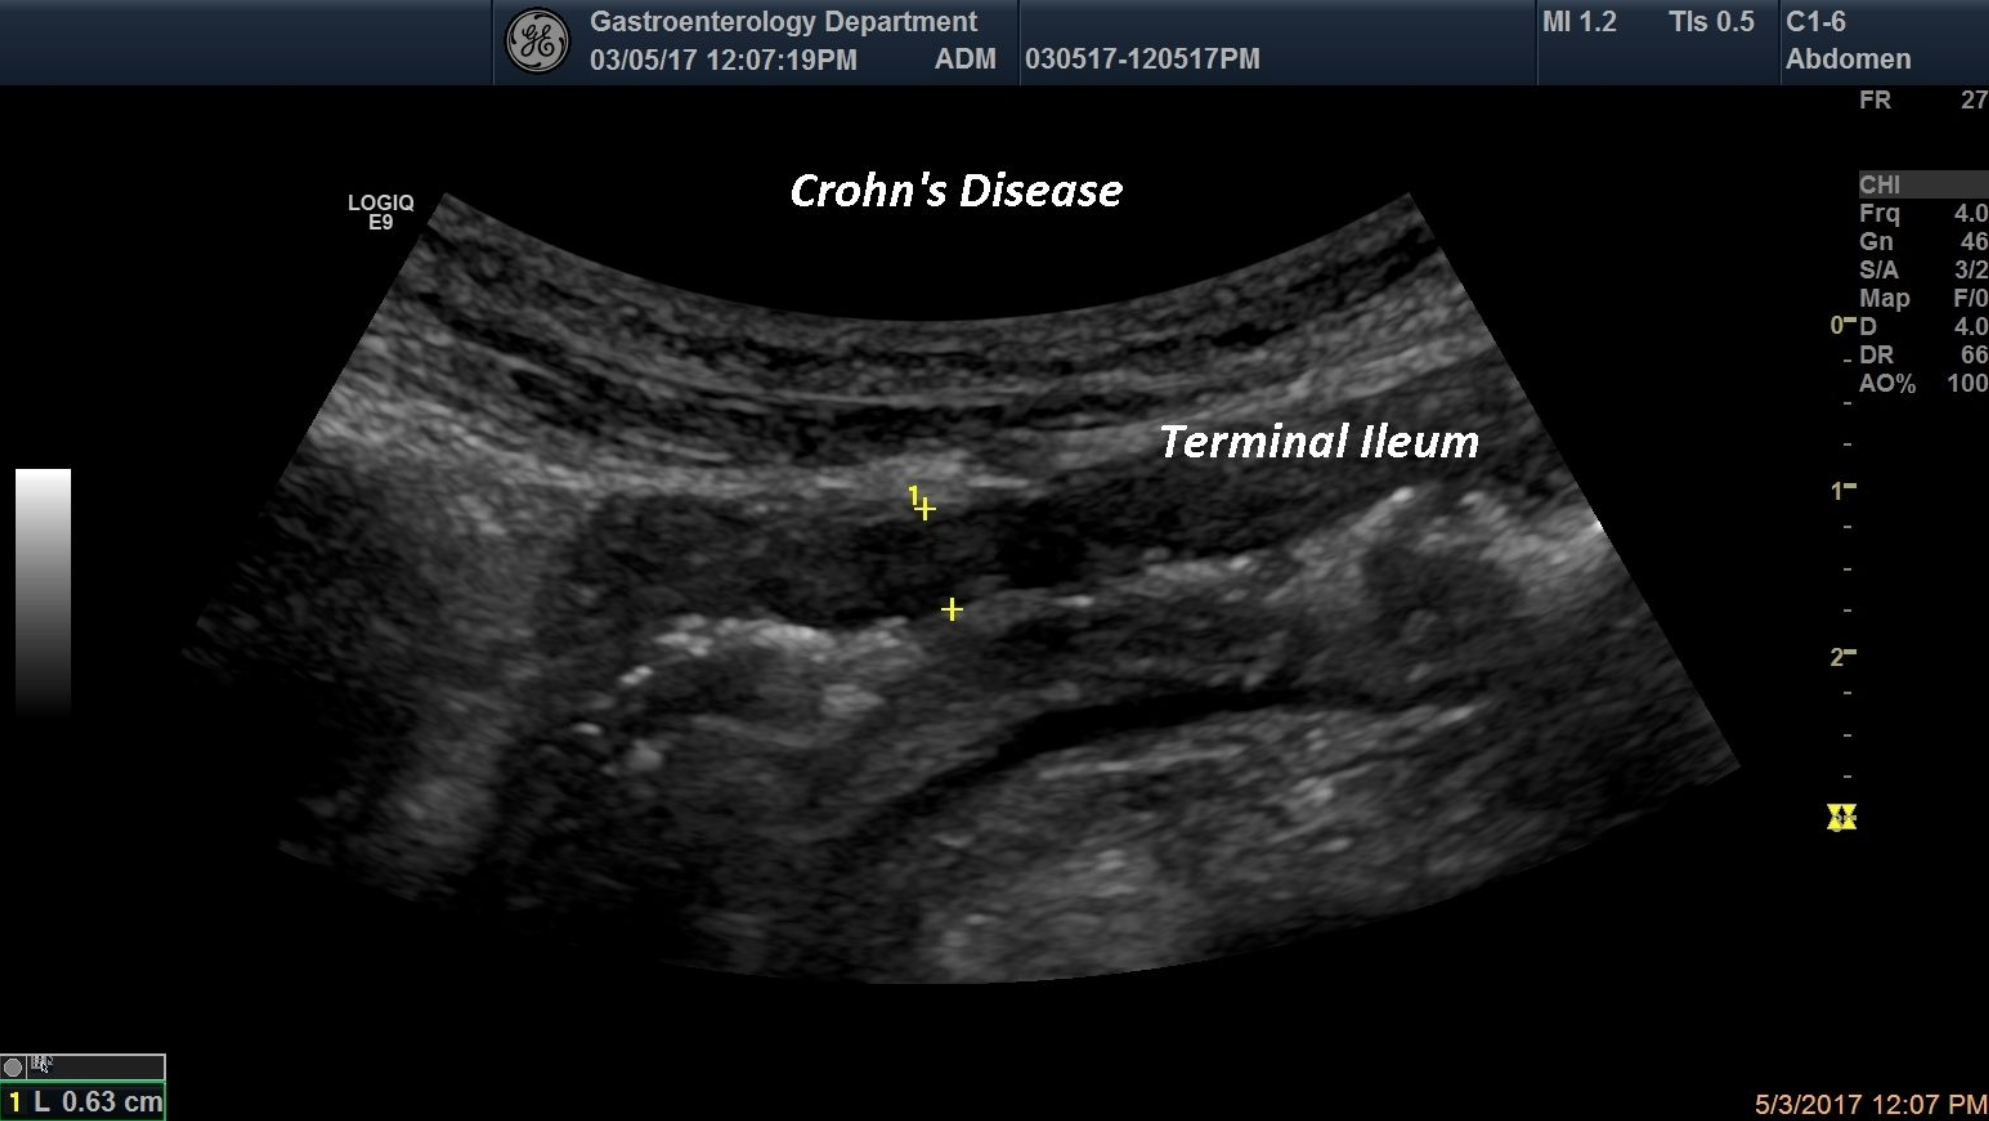

In this ultrasound picture is pointed out the wall thickening and the loss of the multi layer pattern of the terminal ileumin a young patient with chronic diarrhea.

Crohn’s disease, terminal ileum, loss of the multi layer pattern